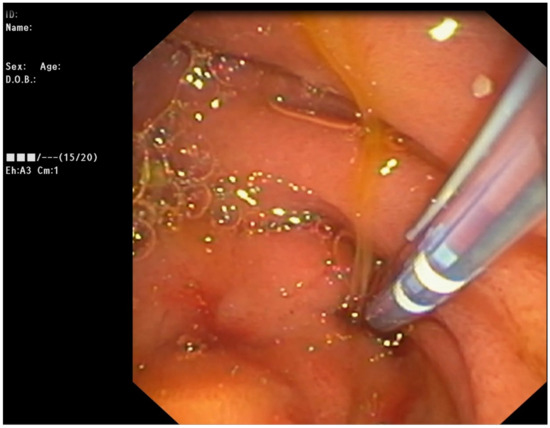

2.3. Endoscopic Management

At six months, the patient was readmitted and ERCP performed electively. Fluoroscopy revealed significant, though incomplete resolution of the stricture at the level of LHD. Further balloon dilation to 10 mm was performed, with subsequent insertion of 3 straight plastic stents—10 fr/6 cm in the 2nd segment branch, 10 fr/6 cm and 8.5 fr/6 cm in the 3rd segment branch. No ERCP-related adverse events were noted.

The patient remained symptom-free for the next 12 months. At one year, elective ERCP was performed. Complete resolution of the stricture was found, with one of the stents proximally migrated in the HD (discussed as an AE in ASGE but not ESGE guidelines). All biliary prostheses were removed with a snare, with the migrated stent being extracted using a standard upper endoscope, which was easily introduced through the fistula.